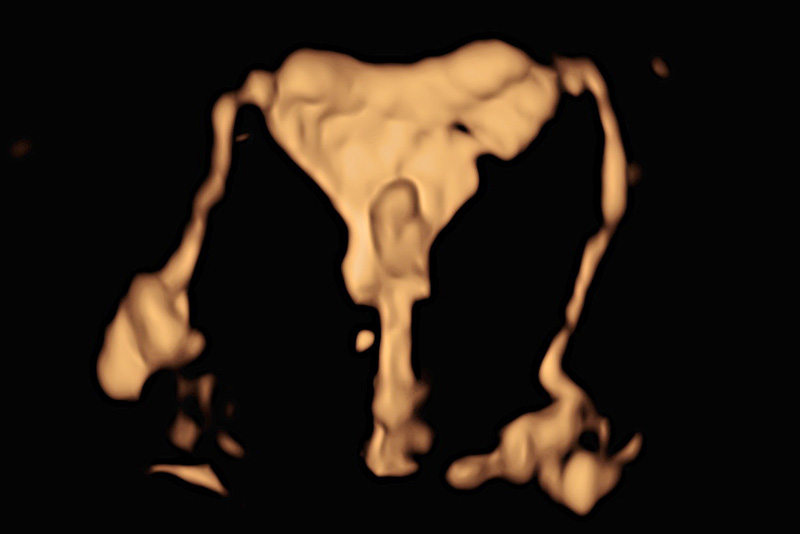

【超声造影实时成像】

子宫输卵管超声造影是观察和评估输卵管通畅度的一种检查方法。这种检查安全、无需麻醉、无创,是不孕不育诊疗过程中最常用的检查手段之一。医生向子宫腔内注入造影剂,通过超声检查实时动态成像,观察宫腔形态和输卵管走行。

因此,这个检查不仅能看到输卵管通不通,还能让整个宫腔充满液体,更清楚地看到宫腔内如息肉,粘膜下肌瘤,宫腔有无粘连、是否畸形。此外,还可以同时排除卵巢疾病等导致不孕的原因,进而诊断宫腔病变和判断输卵管通畅性。